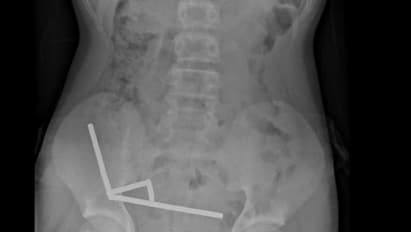

Raio-x abdominal do menino que engoliu entre 80 e 100 ímãs de alta potência (Foto: New Zealand Medical Journal).

Exames revelaram que os ímãs haviam se agrupado em quatro correntes na parte inferior direita do abdômen, unindo diferentes seções do intestino com sua força magnética. A atração dos ímãs era tão forte que chegou a distorcer algumas das imagens dos exames.